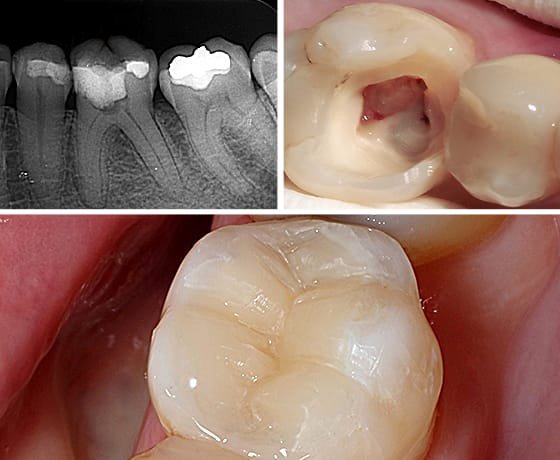

Tratamento do canal dentário, indicado para casos de dor intensa, infecções ou cárie profundas. O objetivo é preservar o dente natural e eliminar a infecção.

Recuperação de dentes danificados por cárie, fraturas ou desgaste, devolvendo função, estética e saúde bucal com restaurações modernas e duráveis.